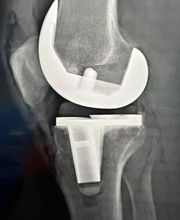

Il Dottor Pera Antonio esercita la professione medica presso il proprio studio ubicato a La Spezia, dove riceve su appuntamento. Pera dr. Antonio è medico chirurgo specializzato in Ortopedia e Traumatologia, anche infantile. Pera dr. Antonio è attualmente iscritto alla S.I.O.T.(Società Italiana di ortopedia e traumatologia); S.I.A.(Società italiana di artroscopia) di cui risulta essere socio onorario; A.L.A.(Associazione ligure di artroscopia); S.I.T.R.A.S.(Società italiana di traumatologia dello sport); S.P.L.L.O.T.(Società piemontese ligure e lombarda di ortopedia e traumatologia); Club di Chirurgia del ginocchio. Dal Gennaio 2012 Pera dr. Antonio svolge il ruolo di Delegato Regionale S.I.A.(Società Italiana di Artroscopia) per la Liguria. Riceve solo su appuntamento.